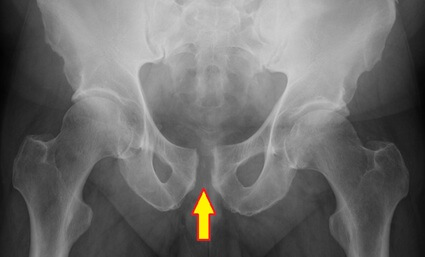

The pubic symphysis is the cartilaginous joint at the center front of the pelvis, where the two halves of the pelvic bone meet, just above the genitals.

The pubic symphysis allows for a small amount of movement, typically around 2–3mm, to aid with activities such as walking and twisting, and plays a crucial role in stabilising the pelvis and absorbing forces during activities.

With symphysis pubis dysfunction, the joint becomes excessively mobile, misaligned or inflamed, often due to hormonal, mechanical, or biomechanical changes. The result is sharp or aching pain in the pubic region, instability, and difficulty with normal movement.